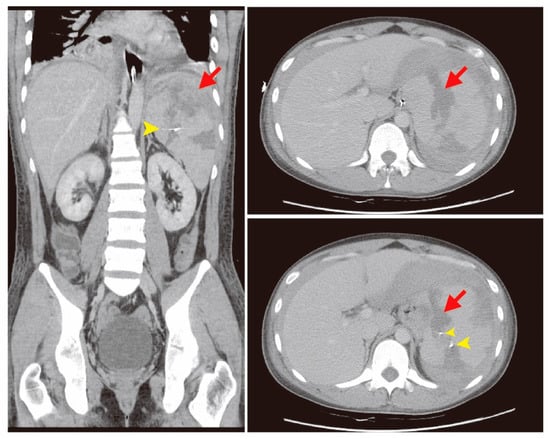

The patient was hospitalized in the intensive care unit (ICU) for post-embolization care. There was no progressive abdominal pain. The follow-up abdominal circumference was decreased, which reflected that intra-abdominal bleeding was under control due to a decreased amount of ascites (Figure 3). The follow-up CT scan revealed the spleen hemorrhage had been controlled through coil embolization (Figure 4). The hemoperitoneum also improved. A bone marrow examination showed sheets of small blasts with scant cytoplasm. Monotonous blasts comprised more than 95% of nucleated cells. ALL with scant cytoplasm was diagnosed with BCR-ABL (+), Periodic acid-Schiff (PAS) (−), peroxidase (−), TdT (< 1%), CD34 (< 1%), CD117 (< 1%), MPO (+, 60%), and CD20 (+, 5–10%). Broad-spectrum antibiotics, including Meropenem, Mycamine, and Teicoplanin, were administered to treat a severe immunocompromised infection due to persistent fever. After supportive care, extubation was performed and the patient stabilized. Target therapy with the agent Dasatinib (50 mg three times per day) combined with chemotherapy agents, including Vincristine and Methotrexate, controlled the progression of ALL. Intrathecal chemotherapy with Methotrexate (15 mg) and methylprednisolone (40 mg) was administered. Bone marrow aspiration and cytology were performed again and revealed normal cellularity. There were no significant side effects or complications. He was regularly followed-up at the outpatient clinic. The follow-up laboratory data is shown in Table 2. A patient consent form has been obtained from the patient.

Figure 3.

Change in abdominal circumference after hospitalization.